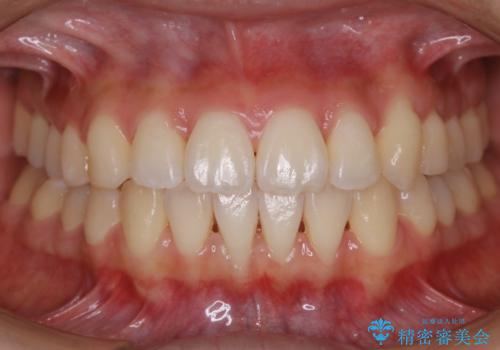

- 上下の歯のガタつきを主訴にご来院されました。

前歯部に特にガタつきが見られ、正中もズレている状態でした。

矯正装置の希望がインビザラインだったため、マイクロインプラントを併用し、奥歯から順に遠心移動をかけていくことにより非抜歯でも主訴のガタつきを治すことができました。

術前・術後の笑った時の歯の見え方の変化にも注目してみてください!

マウスピースとマイクロインプラントを組み合わせることで、抜歯をしなくても歯並びを治すためのスペースを作ることができます。奥歯から順に移動させていくので前歯に変化が出るまでには時間がかかりますが、その分健康な歯を抜歯することなく理想的な歯並びを手に入れることができます。